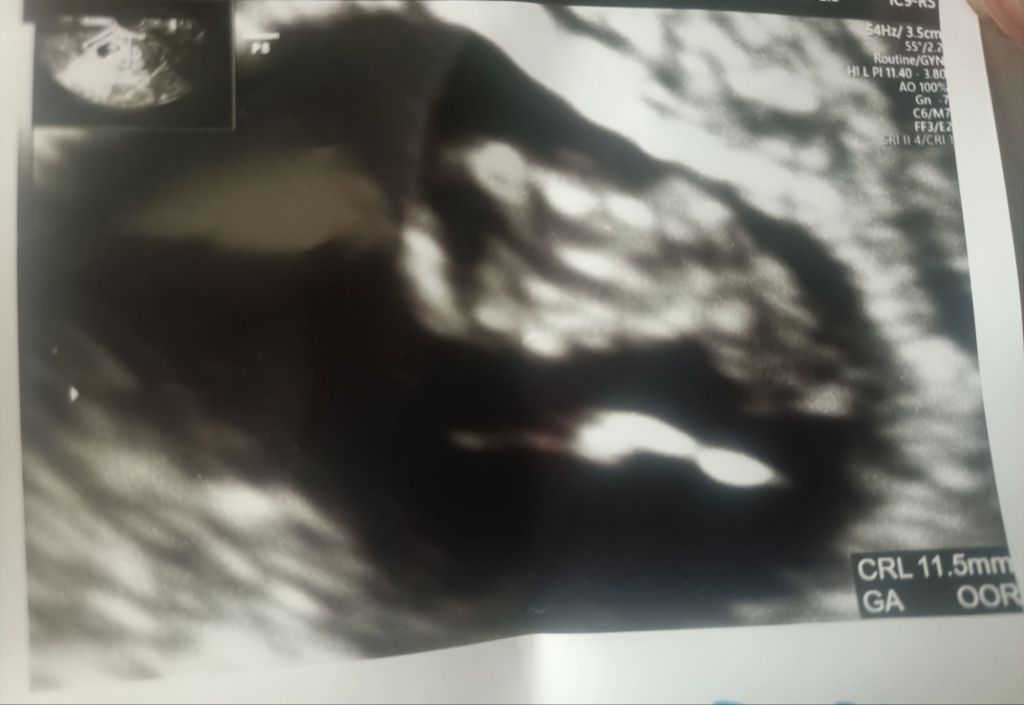

先日の7w3dの心拍確認の様子をお伝えいたします。

心拍確認できました😭✨

エコーが映し出されると、前回よりもすぐに

赤ちゃんになる部分が私にも判別できました。

以前はただの黒い何かだったのに、中に白いものが映っている。

そしてその白い物の色んな長さを図ってる様子。

そうこうしているうちに、一部動いている部分が映って

パクパクパクと

一定のリズムの心音を確認することができました。